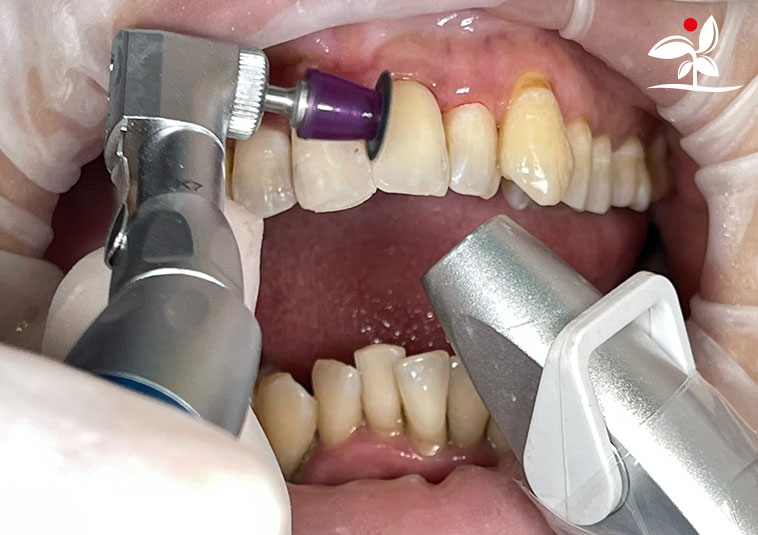

Restoration of Class IV Lesions using Naturomimetic Layering Technique (NLT) and Bioactive Restorative Materials

With the growing awareness about the health, function and aesthetic benefits of preserving natural tooth structure, patients are now globally demanding for aesthetic dentistry with minimally invasive procedures that has a low biological cost. This public demand has encouraged logical clinicians to adopt to the minimally invasive cosmetic dentistry (MiCD) concept and its treatment protocol [1] in their practice. The author has been using MiCD concept and its treatment protocols since 2017, which

include the methods of treatment that are simple, fast, predictable and healthy. In aesthetic restoration, the tooth color restorative materials placement technique is one of the most challenging, confusing and frustrating areas to learn owing to the multiple techniques that have been proposed by many clinicians and replicating such techniques in practice is not always as easy as they are marketed in dentistry. Natural teeth are complex in structure and hard to simulate due distribution of colors through enamel and dentin [2]. Aesthetic restoration strategies should follow proper understanding of defects, right selection of restorative materials along with their proper application, finishing, texturing and polishing [2].